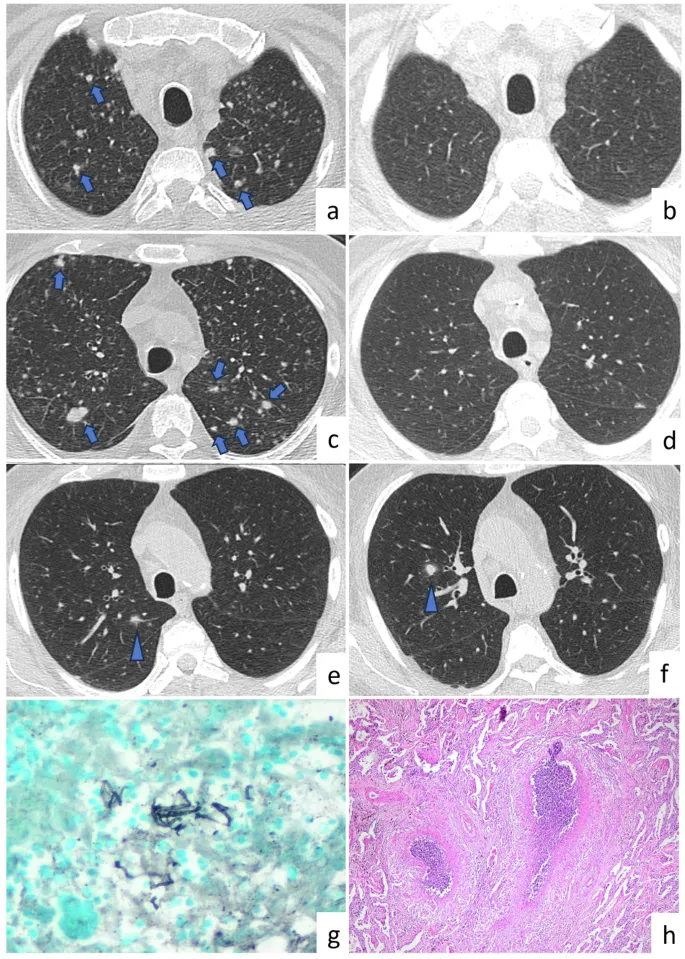

- Diagnosis: CT scan is superior for early detection and detailed assessment; X-ray findings include:

- Upper lobe predominant small, rounded opacities.

- "Eggshell calcification" of hilar lymph nodes (classic).

- Progressive Massive Fibrosis (PMF): opacities >1 cm (general guideline; criteria may vary).

- Silicosis: Sandblasting/mining; egg-shell calcification (hilar nodes), ↑ TB risk; upper lobes.

- CWP: Coal dust; Caplan syndrome (CWP + RA), Progressive Massive Fibrosis (PMF); upper lobes.